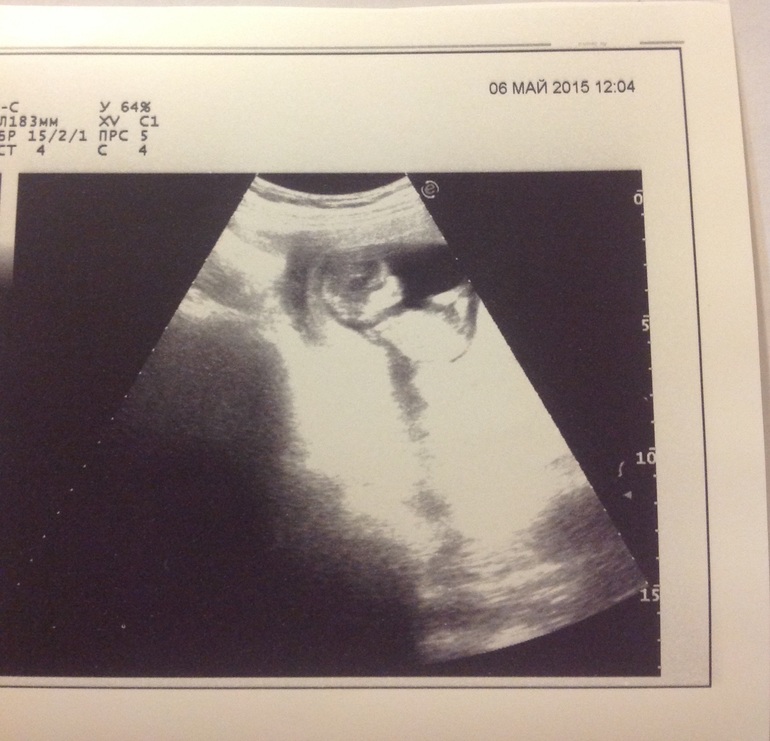

Направила меня моя гинеколог УЗИ почек делать, так как с почками проблемы были в первую беременность перед родами и после. Были отеки и пиелонефрит. Поэтому в эту беременность она решила заранее меня взять на контроль, плюс теперь все беременные с проблемами такого характера должны проконсультироваться в роддоме при 20 ГКБ на Бабушкинской, а там требуют УЗИ, ну вот пришла делать узи. Врач долго искал мою правую почку. Она у меня с детства была опущена, те находилась спереди в паховой зоне, на уровне где обычно аппендицит вырезают. Найти не смог, зато заметил беременность, со всех сторон осмотрел, спрогнозировал мальчика, даже фотку распечатал.

А вот почку нашел намного выше, почти под ребрами, она у меня уплыла, ничего себе так. По факту сказал, что она у меня маленькая, сморщенная и не действующая!! После его слов пребываю в шоке, те рожать мне теперь предстоит с 1 почкой?? И что это значит?? Что показан мне только спец.роддом?? То бишь 20? В котором я впринципе рожать не хотела, да и расположен он на другом конце Москвы. Да, уж.. А может он ошибся.. Или это ничего страшного? Так что посещение оставило двоякое впечатление, с одной стороны как дура рада была, что малыш здоровый и даже мальчик, а с другой озабочена непонятной ситуацией с почками, кстати в левой еще и камни появились, полгода назад не было, но сейчас камни это мелочи..